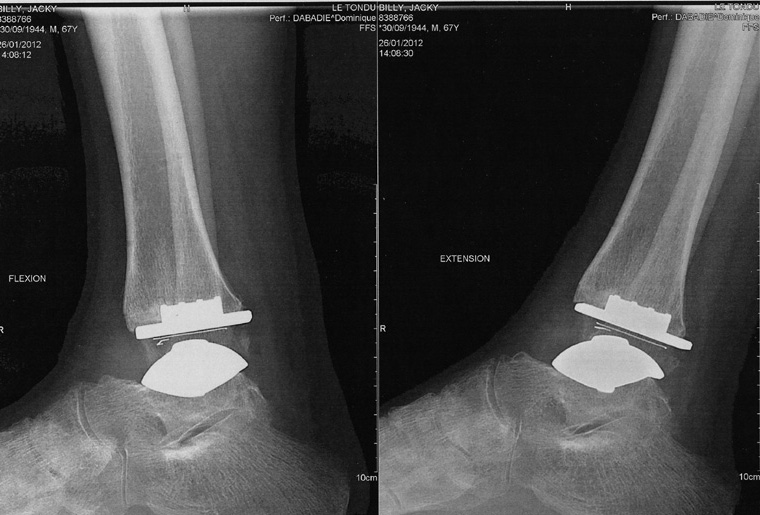

La dernière radio